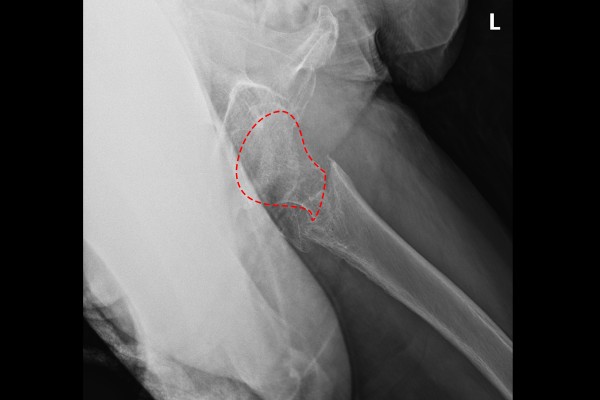

환자분의 정확한 상황을 파악하기 위해 먼저 X-RAY 촬영을 하였고, 촬영한 X-RAY에서 정상적인 우측 고관절목과 다르게 좌측 고관절목이 골절된 것이 확인됩니다.

측면에서 확인해보아도 고관절목이 부러져있는 것이 확인됩니다.